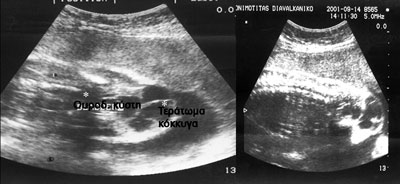

Εικόνα 4. Καλόηθες τεράτωμα κόκκυγος νεογνού στο πρώτο 24ωρο της ζωής του, εξωρμόμενο από της εξωτερική επιφάνεια του κόκκυγα..

Εικόνα 5. Καλόηθες τεράτωμα τρείς μήνες μετά τη χειρουργική του αποκατάσταση η οποία έλαβε χώρα την 2η εβδομάδα μετά τη γέννηση (η ίδια περίπτωση με την εικ. 4).